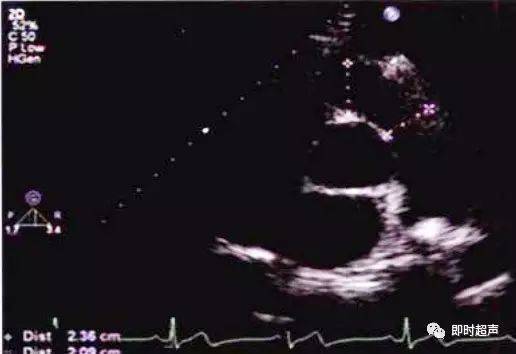

图解二维超声心动图正常值与测量